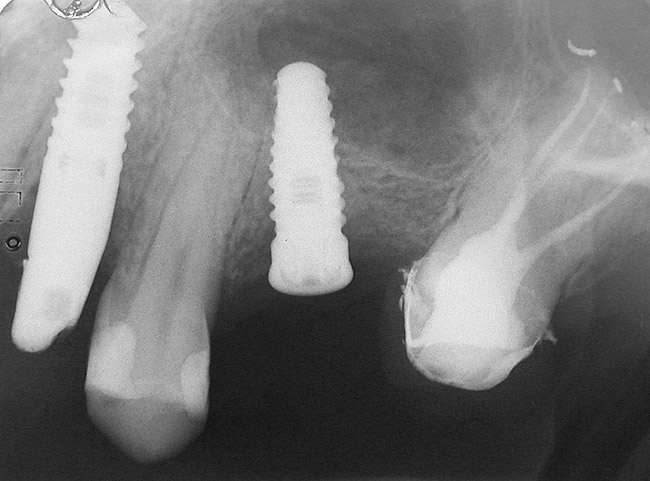

A 55-year-old male was referred for implant placement and prosthetic rehabilitation in the area of tooth No. 15. The tooth had been extracted 4 years prior. The radiograph revealed inadequate bone height for implant positioning (Figure 6). It was decided to insert an implant that was 11.5 mm in length and 3.75 mm in diameter, performing a slight osteotomic maxillary sinus lift. A heterologous bone graft also was planned to obtain a larger sinus lift.

A full-thickness mucoperiosteal flap was raised, and alternating osteotomes were used to prepare the implant site. After achieving a length of 7 mm (Figure 7A and Figure 7B), heterologous bone graft was implanted and the osteotome sequence was repeated. The implant showed primary stability.

Second-stage surgery was performed after 4 months (Figure 8); healing abutments were placed and the soft tissue was allowed to heal for 5 more weeks. Then, splinted porcelain-fused-metal (PFM) crowns supported by custom gold abutments were delivered (Figure 9 and Figure 10).

Figure 7a  Alternating osteotomes with variable conicity used to perform the alveolar remodeling in the area of tooth No. 15.

Figure 7a

Figure 7b  Alternating osteotomes with variable conicity used to perform the alveolar remodeling in the area of tooth No. 15.

Figure 7b

Figure 8  At 4 months after treatment, the radiograph revealed the presence of a bone layer surrounding the implant.